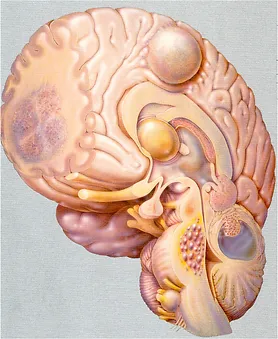

Tümörler iyi huylu (benign) ve kötü huylu (malign) olarak iki ana guruba ayrılırlar. İyi huylu tümörler kanser hücreleri içermeyen gruptur. Genellikle çıkartılabilirler, tekrarlamazlar ve etraftaki normal çalışan dokulara yayılıp onların fonksiyonlarını bozmazlar. İyi huylu beyin tümörlerinin iyi sınırları vardır ve cerrahi ile çıkartılabilirler. Ancak beyin içindeki diğer normal dokulara bası yaparak onların normal çalışmasını engelleyebilirler.

Kötü huylu beyin tümörleri kanser hücreleri içermektedir. Hayatı tehdit ederler. Hızlı büyürler ve etraf normal dokulara yayılarak onların fonksiyon görmesini de engellerler. Genellikle tıpkı ağaçlar gibi etrafa kök salarak beslenmeleri için gerekli olan maddeleri sağlıklı beyin dokusundan çalarak ayakta kalırlar.

Santral sinir sitemi, özellikle de beyin çok sıkı korunan kapalı bir kutunun (kafatası) içinde olduğundan basınç değişikliklerine çok hassastır. Bu nedenle bazı iyi huylu tümörler de kanser hücresi içermemelerine rağmen önemli yapılara baskı yaparak hayati tehlikeye neden olabilirler.

Beyin dokusundan kaynaklanan tümörlere birincil (primer) beyin tümörü denilir. İkincil (sekonder) beyin tümörü ise beyin dışı bir kanserin beyne yayılması ile oluşur. Beyin tümörleri kaynak aldıkları dokunun tipine göre adlandırılırlar. En sık görülen birincil beyin tümörü gliomlardır. Bunlar beynin sinir dışı destek hücrelerinden kaynaklanır.